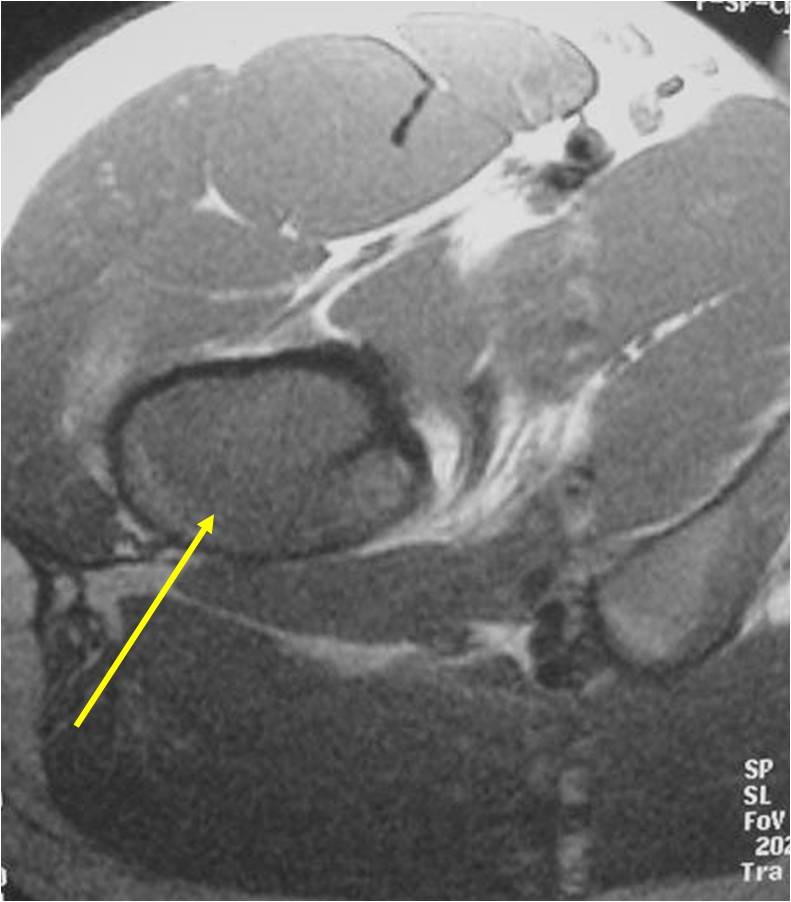

- Most commonly arises from diaphysis but can also arise from metadiaphysis and metaphysis;

- Femur: Single most common site

- Soft Tissue Mass in 90% of of cases

- Ewing sarcoma is one of the most aggressive tumors

- High propensity for Local recurrences